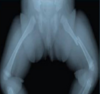

Q-l The given x ray show one of the following: a- Non closure of epiphyseal line between pubic ramus and ischeal ramus b- Fusion of epiphyseal lines between head of femur and shaft c. Non of the above between ishceal, pupic, ileac bones d- Non closure of epiphyseal line

d- Non closure of epiphyseal line

221

Q2 -The estimated age is: a- Above 15 years old. b- Above 18 years old. c- Less than 15 years old. d- Less than 20.

c- Less than 15 years old.

222

Q3-The given x- ray show one of the following: a- Closure of epiphyseal line between head of the femur and shaft. b- Non closure of epiphyseal line between head of the femur and its shaft. c- Non closure of epiphyseal line between pubic and ischeal rami. d-All of the above.

a- Closure of epiphyseal line between head of the femur and shaft.

223

Q4 -The estimated age is: a-Above 18 years old. b-Less than 18 years old c-Above 20 years old. d-Above 23 years old.

a-Above 18 years old.